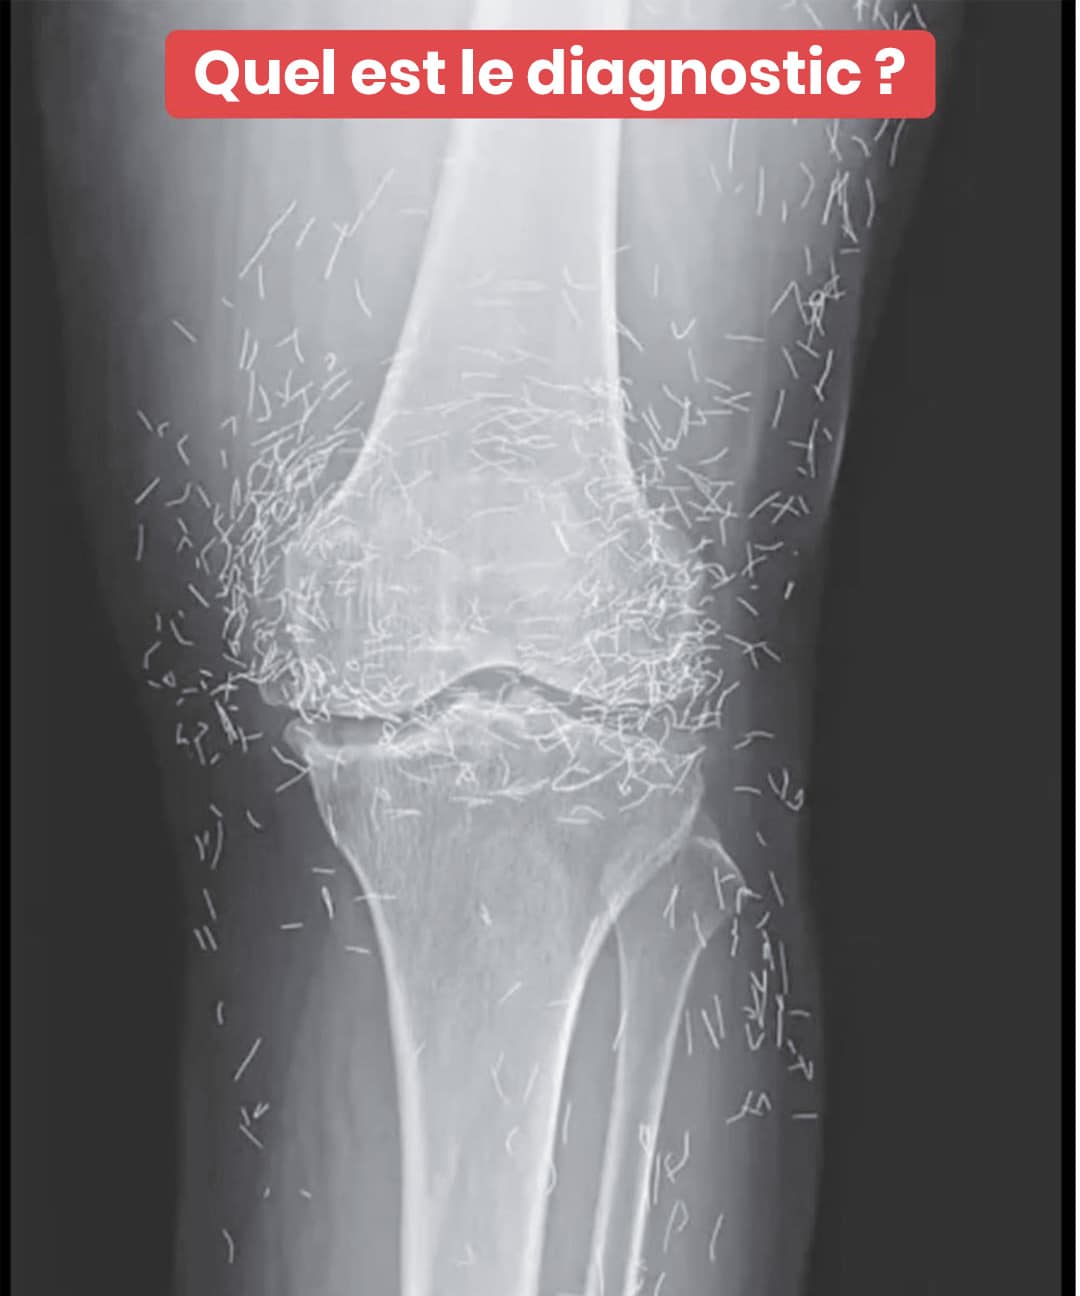

Une patiente découvre un trésor insoupçonné dans ses genoux grâce à une radiographie

Lors d'un examen d'imagerie médicale banal, une femme a fait une découverte pour le moins surprenante : ses articulations dissimulaient des centaines de fragments métalliques scintillants. Cette révélation extraordinaire soulève des questions fascinantes sur une pratique thérapeutique méconnue en Occident. Plongez dans cette énigme médicale aux allures de trésor caché.

C’est à l’occasion d’un examen d’imagerie standard que les praticiens ont observé, stupéfaits, des centaines de petites pointes brillantes éparpillées autour de ses articulations du genou. Une véritable singularité clinique qui a provoqué autant d’émerveillement que de circonspection. Car si l’or présente une excellente tolérance biologique, la persistance d’éléments exogènes dans l’organisme n’est jamais dénuée de conséquences.

Selon des experts en radiologie, ces implants métalliques peuvent occulter certaines structures anatomiques sur les clichés radiologiques, compromettant le dépistage d’autres affections. Plus préoccupant encore, ils rendent problématique la réalisation d’une IRM : le danger de mobilisation des aiguilles sous l’influence du champ magnétique existe bel et bien, avec un potentiel de lésions tissulaires.